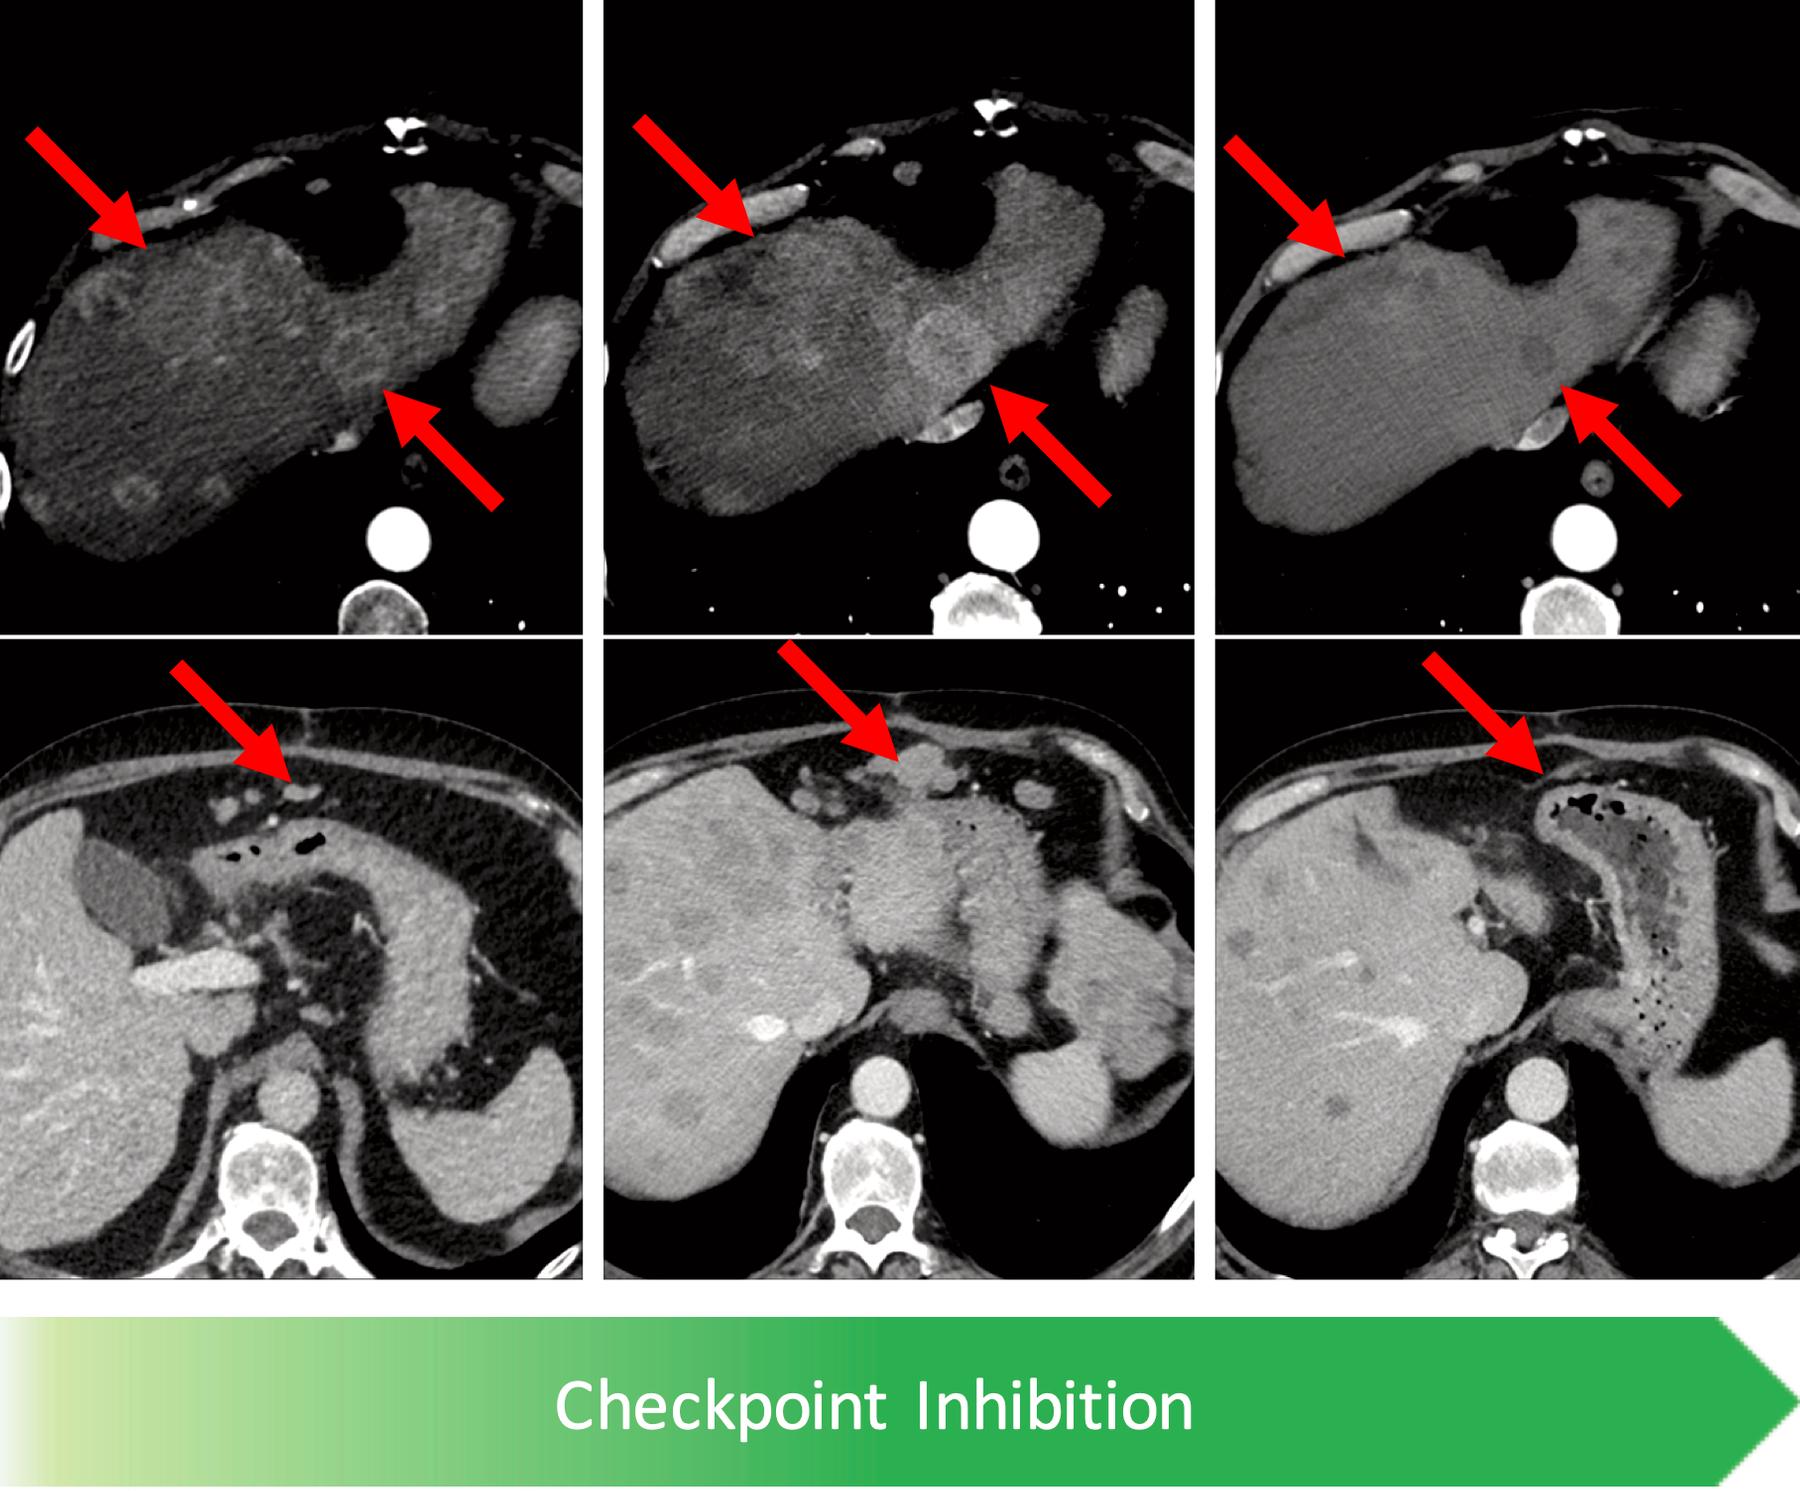

Besondere Schwerpunkte bestehen darüber hinaus durch Zentren des Klinikums der supraregionalen Versorgung, darunter z. B. für Sarkome, neuroendokrine Tumore und auch für die immun-onkologische Therapie. Hierdurch besteht eine langjährige Erfahrung in der Identifikation atypischer Muster des Therapieansprechens.

Zu den weiteren Aufgaben der onkologischen Bildgebung zählt auch das Toxizitäts-Monitoring, zum Beispiel von Immuntherapien wie der Checkpoint Inhibition oder der Chimeric Antigen Receptor (CAR) T-Zell Therapie.